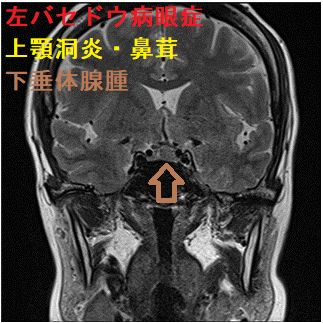

バセドウ病眼症(甲状腺眼症)診断目的のため行った眼窩MRI検査で、偶然、下垂体腺腫が見つかる場合があります。下は、左眼バセドウ病眼症(眼筋炎)、下垂体腺腫、上顎洞炎・鼻茸が合わせて見つかったケースです。下垂体腺腫が視神経交叉を押し上げているため、病態は複雑になります。